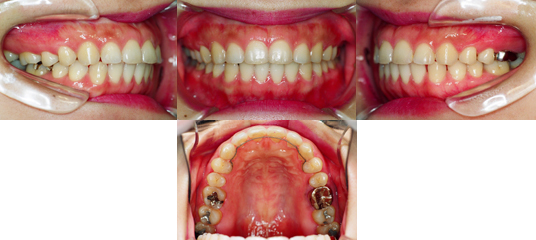

| 治療タイプ | 部分矯正 |

| 主訴 | 前歯のすき間を治したい |

| 性別 | 女性 |

| 治療開始時年齢 | 27才7か月 |

| 診断名 | 上顎前歯部空隙 |

| 使用装置 | 上顎セクショナルアーチ |

| 抜歯or非抜歯 | 非抜歯 |

| 治療期間、 治療回数、治療費 |

4か月、4回、187,500円(消費税導入前) *動的治療終了まで |

| 矯正歯科治療における偶発症 | 一般的に、歯肉退縮、歯根吸収、齲蝕のリスクが 挙げられています。 → 一般的なリスク・副作用 本症例では臨床上問題となる症状は認められ ませんでした。 |